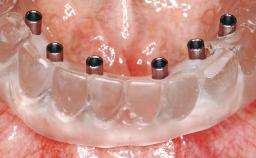

Conventional Loading of Eight Implants in the Maxilla and Final Restoration with a Full-Arch Gold-Ceramic FDP

# of Implants 8

Type of Implants One-Piece

Loading Protocol Conventional or early

Interim Prosthesis during Healing Removable Removable